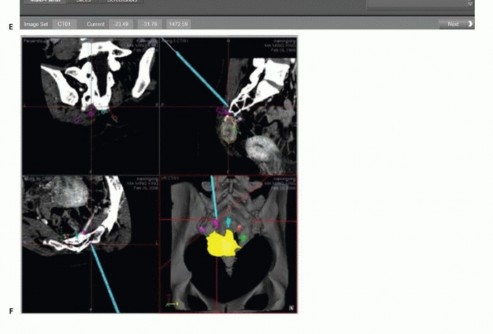

التخطيط قبل الجراحة

يُعد التخطيط الدقيق قبل الجراحة أمرًا حاسمًا لنجاح العملية. يقوم الأستاذ الدكتور محمد هطيف بمراجعة شاملة لجميع صور ما قبل الجراحة (الأشعة السينية، التصوير المقطعي، الرنين المغناطيسي، تصوير الأوعية الدموية) لتحديد خطة جراحية واضحة وتقييم الدواعي والمخاطر.

- تحديد مدى الاستئصال: يجب تحديد المدى العلوي للاستئصال بدقة لتحقيق استئصال فعال. الهدف هو إنقاذ أكبر عدد ممكن من الأعصاب العجزية مع الحفاظ على هوامش جيدة.

- التقنيات المتقدمة: في الحالات التي يتم فيها التخطيط لجراحة بمساعدة الملاحة الحاسوبية، يتم دمج صور التصوير المقطعي والرنين المغناطيسي وتصميم الجراحة بالتفصيل.